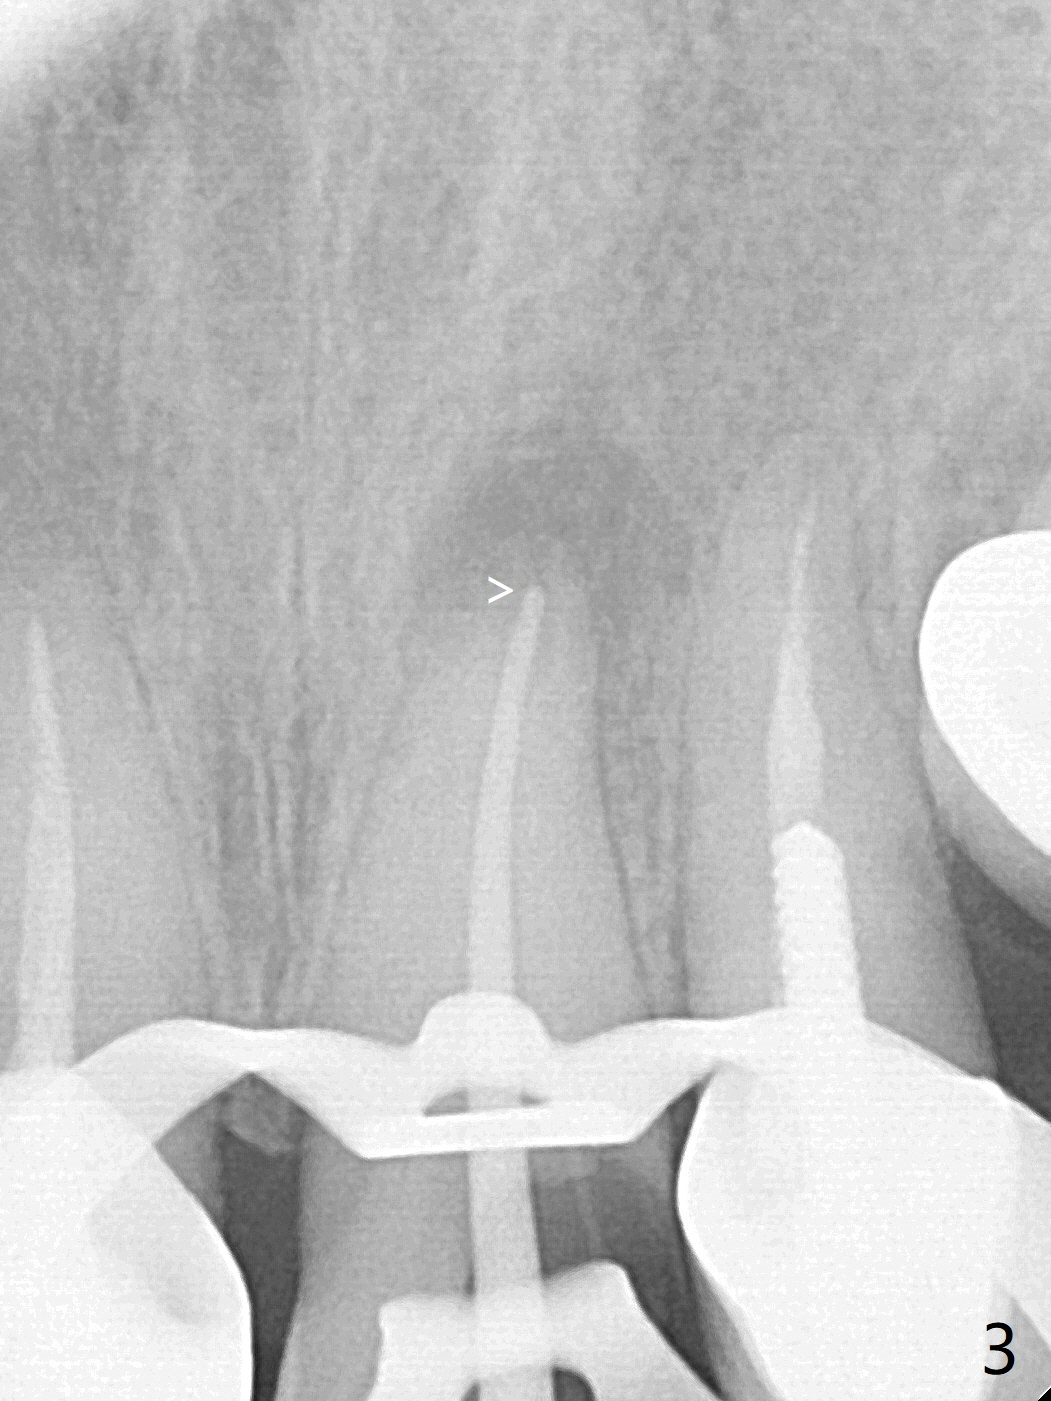

62岁女因牙痛(图一)做根管治疗(图二,三)。一年10个月后因11,13,30,31 植牙,拍摄CT,根尖阴影明显缩小(图四,五)。颊侧骨板薄而短(图四:>),牙槽骨也狭窄,如果需要植牙,比较困难。